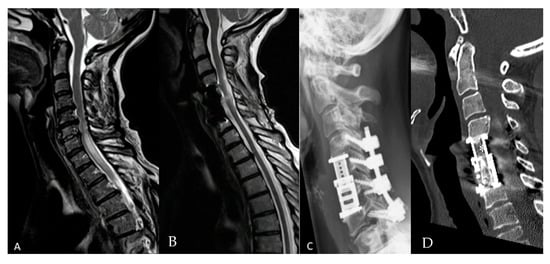

2. Materials and Methods

3. Results

3.2. Radiological Outcome